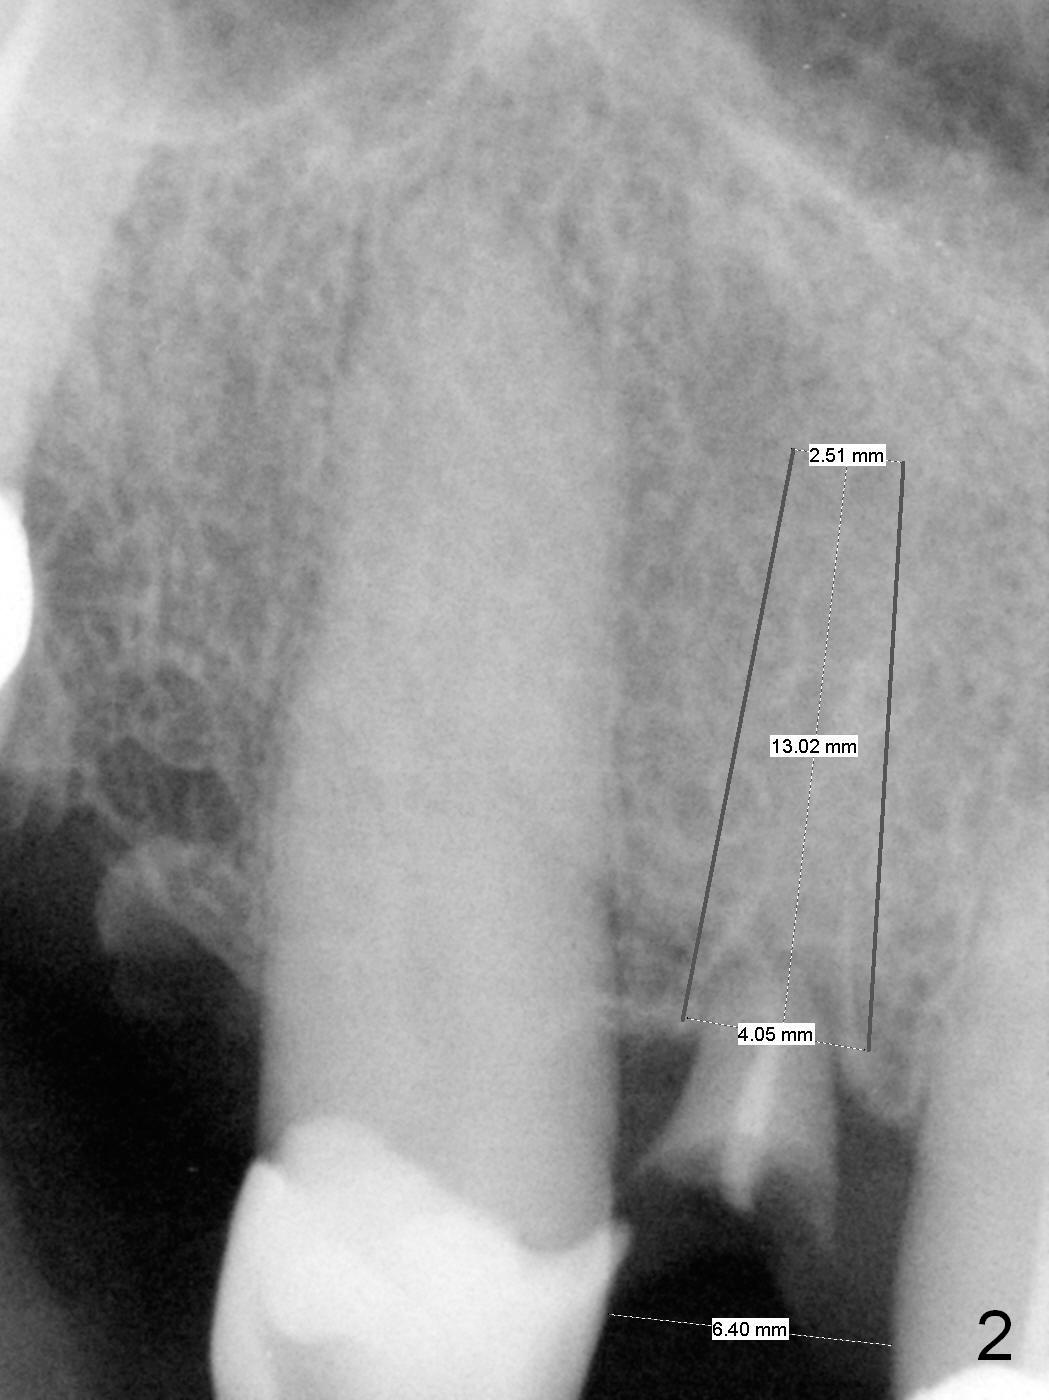

A 59-year-old man (used to be coke drinker) has several missing teeth and residual roots. He wants to get rid of a loose flipper for #7, which is incisally (Fig.1 arrow) and labially (take preop photos) displaced. When it is extracted with curettage of apical granulation tissue (Clindamycin), the socket may not be completely exposed, especially palatally. Do not hesitate to make incision for better visibility and precise osteotomy. If the mesiodistal width of the edentulous space is more than 6.4 mm (Fig.2), use 1.6 mm pilot drill. Otherwise consider 1-piece implant. Pay attention to bone density while drilling. The initial depth will be 10 or 11 mm. PA is to be taken for trajectory and depth confirmation. To prevent periimplantitis, make sure that the first coronal thread is below the labial crest. Due to several missing teeth with insufficient posterior support, the immediate provisional should have daylight clearance. CT shows that 3.8 mm wide implant is appropriate for the buccopalatal width (Fig.3). Retrospectively, the implant could be smaller or to be placed more palatal. If the bone density is low, the implant could be longer than 13 mm.